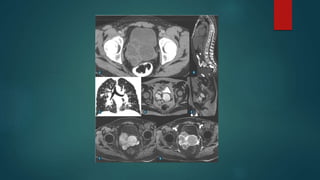

VESICULITE SEMINAL AGUDA

 Geralmente secundária a prostatite bacteriana e apresenta-se na

US, TC ou RM com espessamento parietal ,além de impregnação

parietal difusa pelo contraste na TC e RM.

ABSCESSO

 Normalmente decorre por manipulação cirúrgica ou extensão

direta de abscesso prostático .